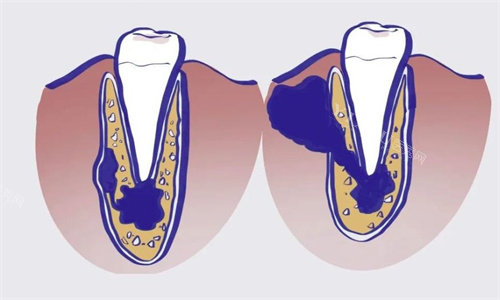

医院的一大特色就是 “中西方结合应急法”,要是孩子磕断牙了,医生不仅会教家长保存牙齿的方法,还推荐儿童牙外伤急救包,里面连固定牙齿的牛奶都备好了。有家长反馈,这套方法特别实用。

医院在儿童口腔疾病的治疗上,有着可靠的医生和设备,能处理像儿童牙齿外伤、急性牙髓炎等急诊情况 。